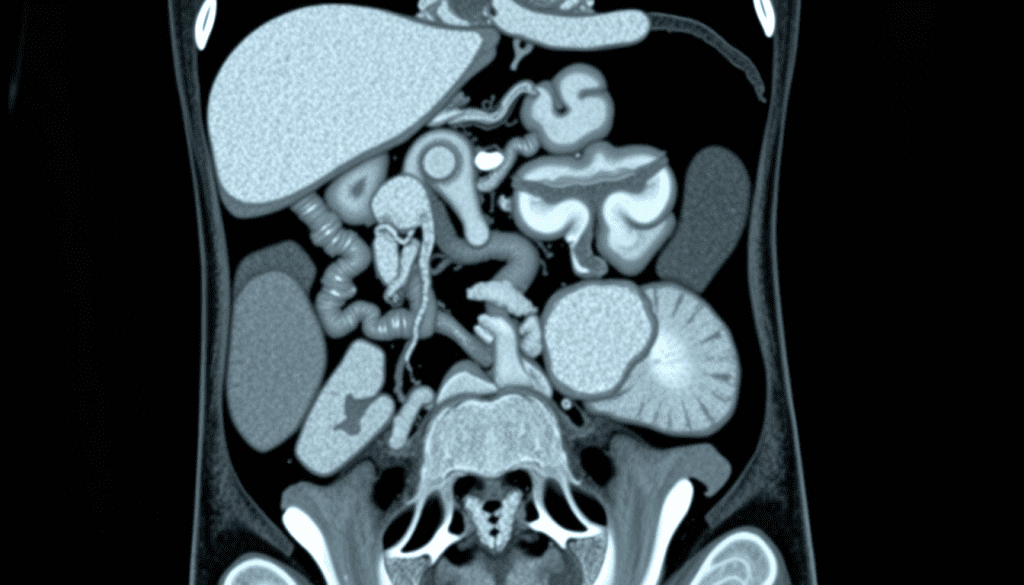

The Role of CT Scans in Evaluating Abdominal Pain

When people haveabdominal pain, CT scans are key in finding the cause. Pain can come from many things like inflammation, infection, or cancer. It’s hard to figure out without seeing inside the body.

CT scans give us detailed pictures of the abdomen. They help us find where the pain is coming from. This guides us on how to treat it. CT scans are very useful in both emergency and regular check-ups.

Often, we start with a CT scan for abdominal pain. CT scans show everything inside the abdomen. They are fast and accurate, which is important in emergencies.

CT scans help us tell apart different causes of pain. This is key for the right treatment.

CT Scan Abdomen Cancer: Detection Capabilities

Abdominal CT scans are key in finding and managing abdominal cancers early. They give us detailed images of the belly area. This helps us spot and understand different cancers.

What Cancers Can an Abdominal CT Scan Detect

These scans can find many cancers, like liver, pancreatic, kidney, and colon cancers. They show these organs clearly. This lets us see tumors and how big they are.